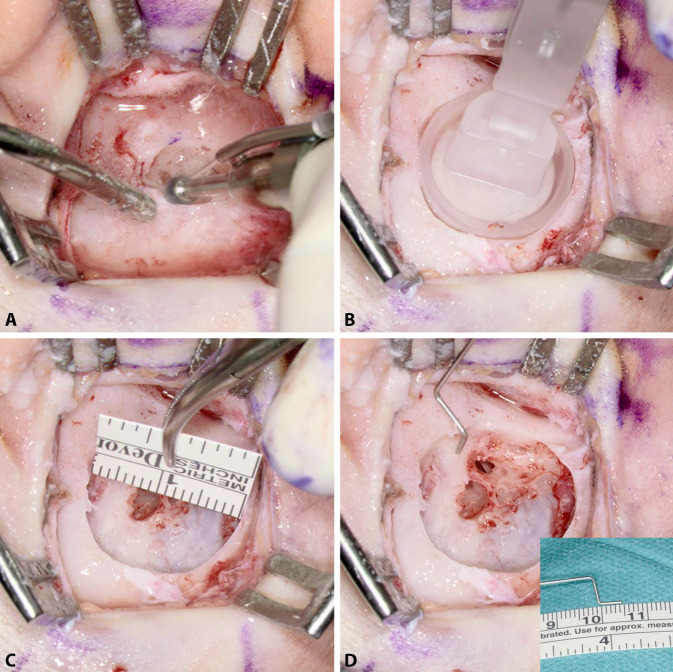

Next, only the implant bed for the BC-MFT is drilled. Despite careful preoperative planning, the implant bed might reach the dura, the sigmoid sinus, an ear canal remnant, or an open mastoid cavity. Therefore, the authors typically start by drilling the implant bed in the center of the BC-FMT position to a depth of 4.5 mm with a small-diameter drill bit, approximately 5 mm in diameter. The implant bed is then gradually enlarged. By successively moving the drill bit away from the structures mentioned, they can be avoided (Fig. 4A). The adequate size and shape of the implant bed can be evaluated with a sterile “BCI 602 Sizer Kit” (Fig. 4B). Alternatively, an adapted sterile ruler and an intraoperatively “created” depth gauge (the authors use a 0.7-mm suction tip, off-label) have proven useful for this measurement (Fig. 4C, D).

Fig. 4.

Creating the implant bed. A Drilling of the implant bed is started in the center of the position planned for the bone conduction-floating mass transducer. The depth is 4.5 mm and the diameter is relatively small, approximately 5 mm. The implant bed is successively enlarged by moving the drill bit away from critical structures (sigmoid sinus, dura, ear canal, open mastoid cavity) to avoid damage. B The adequacy of the size and shape of the implant bed can be evaluated with a sterile “BCI 602 Sizer Kit.” Alternatively, the implant bed can be measured with a sterile ruler and a depth gauge (here, the authors used a 0.7-mm suction tip, off-label) (C, D)